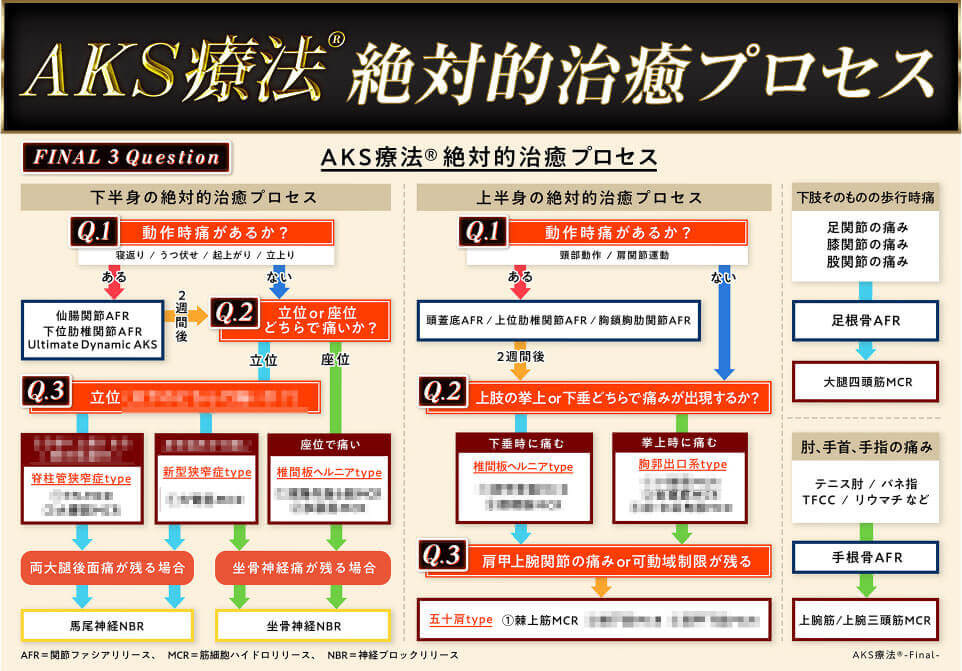

これが、AKS療法®の絶対的治癒プロセスです。この図は患者さんが来た時の問診時に使えるフローチャートになっており、あなたは上半身、下半身それぞれに対応する3つの質問「Final 3 Qestion」を患者さんに聞き、絶対的治癒プロセスに則ってチャートを進むだけで、原因が明確になり、アプローチする手技が明確になるのです。

手術宣告された重症患者さんを改善させるために

あなたがやることはたったこれだけ!

- ①フローチャートに沿って誰でも出来る3つの質問をする

⇒医師も分からない真の症状の原因が浮き彫りに! - ②チャートから導き出された手技をやるだけ

(手技自体は非常にかんたんなのでご安心ください)

かんたん2ステップでどんな重症患者さんも

改善できるようになったらいかがでしょうか?

この絶対的治癒プロセスを使えば、たとえあなたが解剖学をまったく知らない素人だとしても、患者さんの痛みの真の原因が分かるようになるので、原因が分からずに全身を揉んでみたり、治療に悩んだり不安になることがなくなるのです。

実際に私もこのプロセスを使って患者さんの問診を行ったからこそ、原因が明確になり、患者さんを回復に導くことが出来たのです。

つまり、この絶対的治癒プロセスはゴッドハンドと同じ診立てや問診、治療計画を立てるためのカンニングペーパーのようなものであり、手技の使い方をナビゲートしてくれるものです。

様々な治療法がありますが、手技のやり方を教えてくれる教材やセミナーはあっても、ここまで確固たる手技の使い方が体系化されて、プロセスチャートとしてまとまっている治療法はなかったのではないでしょうか。

この絶対的治癒プロセスがあることで、患者さんと原因を明確にしながら治療を進めていけるので、患者さんの信頼も獲得できます。

患者さんは、「病院でもここまで明確に原因を教えてくれなかった!」と、絶対的治癒プロセスを使ったあなたの問診に喜んでお金を払ってくれるようになるのです。